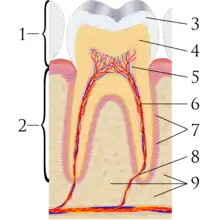

Dentistry, also known as dental medicine and oral medicine, is the branch of medicine focused on the teeth, gums, and mouth. It consists of the study, diagnosis, prevention, management, and treatment of diseases, disorders, and conditions of the mouth, most commonly focused on dentition (the development and arrangement of teeth) as well as the oral mucosa.[2] Dentistry may also encompass other aspects of the craniofacial complex including the temporomandibular joint. The practitioner is called a dentist.

- Endodontics (also called endodontology) – Root canal therapy and study of diseases of the dental pulp and periapical tissues.